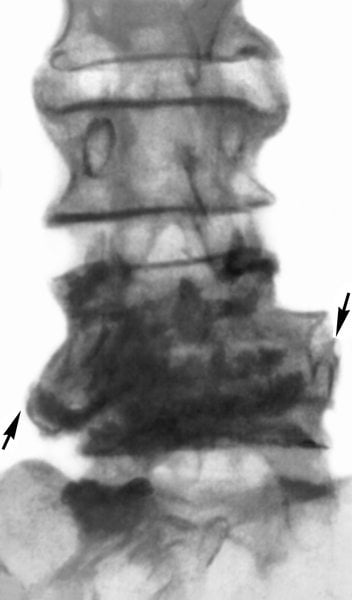

Основная причина развития этого заболевания — полиморфные грамположительные микроорганизмы рода Brucella. От их разновидности зависит характер и выраженность возникающих симптомов. Наиболее тяжело протекает спондилит, спровоцированный Brucella melitensis. Он развивается на поздних стадиях бруцеллеза и чаще всего наблюдается при хроническом рецидивирующем его течении. Патологией обычно поражаются поясничные сегменты, реже — шейные.

- рентгенография в прямой и боковой проекциях;

- КТ или МРТ;

- радионуклидная томография или рентгенография.